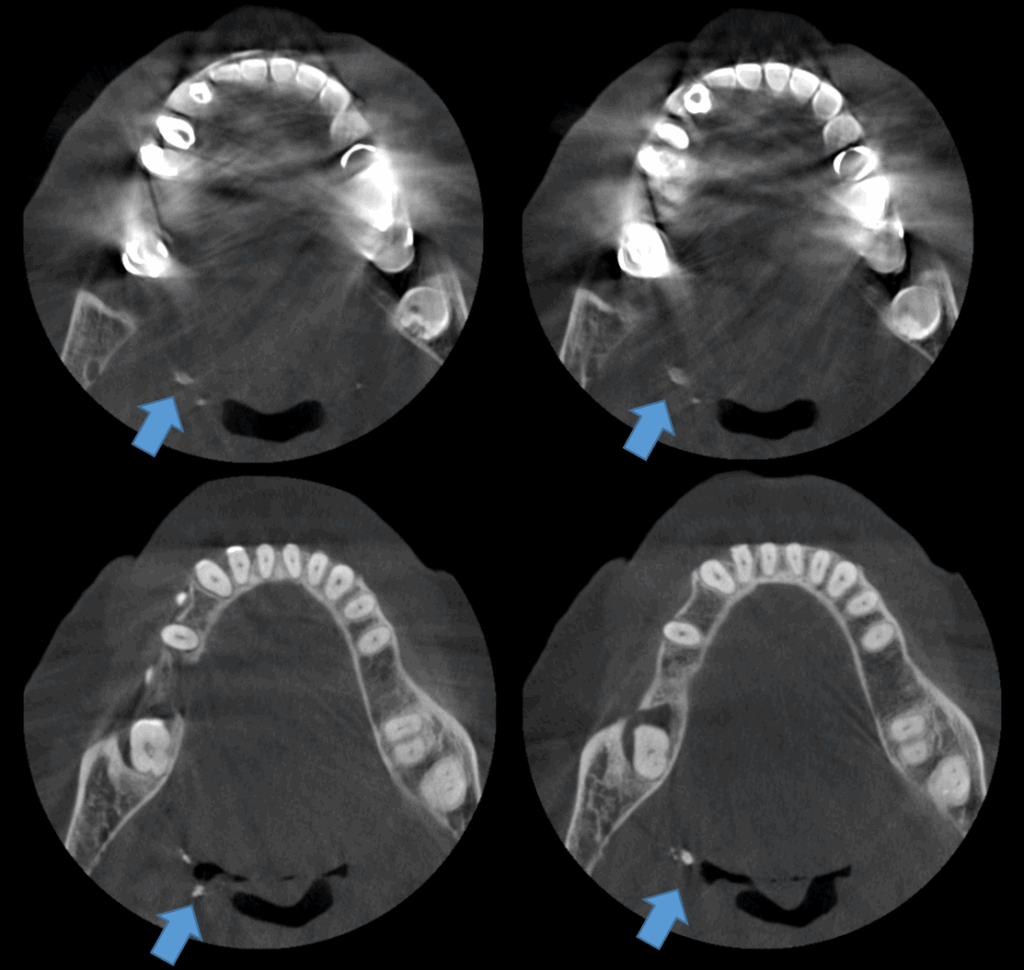

A la evaluación de la tomografía de campo mediano se observan dichas imágenes hiperdensas múltiples, de forma irregular y densidad cálcica en el espacio parafaringeo, a predominio del lado derecho. Signos imagenológicos compatible con cálculos amigdalinos o tonsilolitos.

CORTES AXIALES